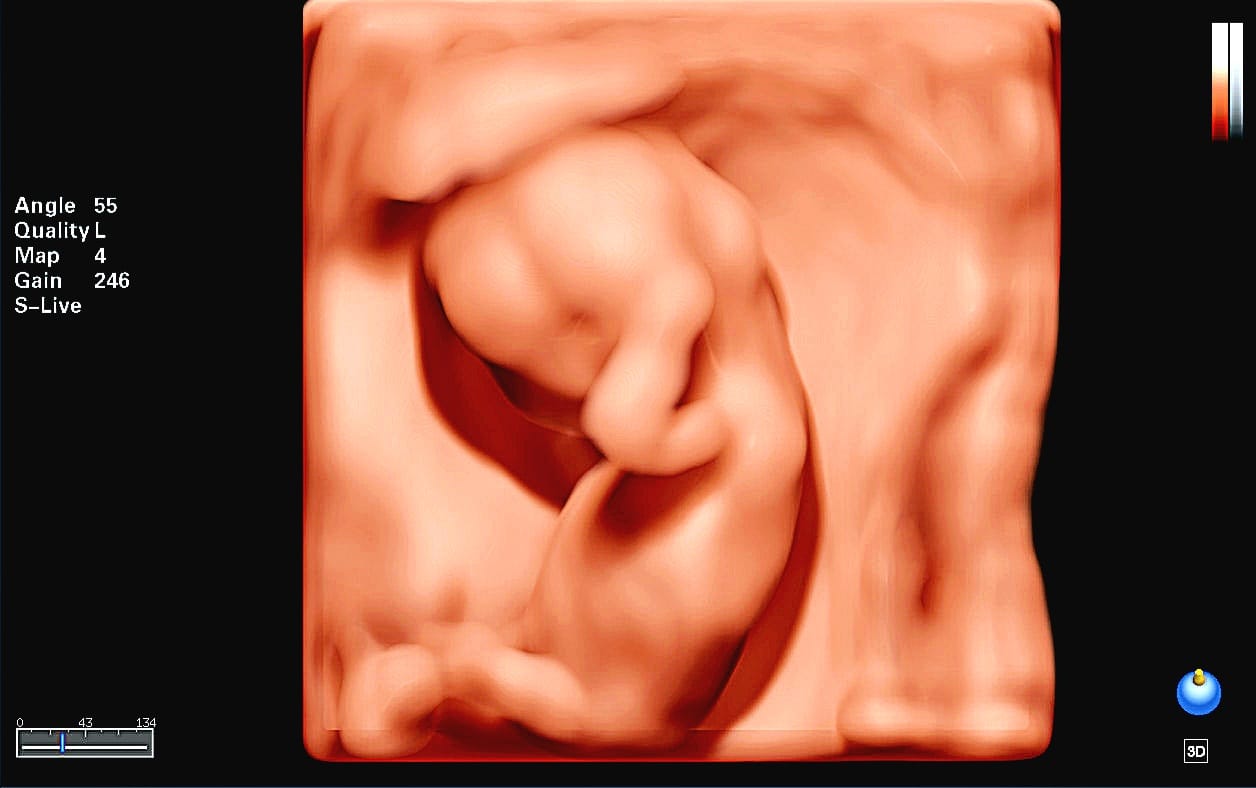

- Te proporcionamos tecnología en alta resolución, con la cual podrás ver una imagen a color en tiempo real de tu bebé ,proporciona una visión temprana y más transparente de la anatomía fetal, va más allá de la superficie para revelar hasta sus huesitos, órganos y otras estructuras internas, aportando una mayor capacidad de diagnóstico.

Esta ecografía se realiza desde las 11 semanas hasta las 13 semanas + 6 días. La exploración generalmente se realiza por vía transabdominal, pero en algunos casos puede ser necesario realizar el examen por vía Transvaginal. Esta es una de las exploraciones más importantes durante el embarazo y nos ayuda:

La exploración se realiza entre las 18 y 24 semanas de gestación. Ideal 20 a 22 Semanas de gestación. Durante la exploración, examinamos cada parte del cuerpo fetal, determinamos la posición de la placenta, evaluamos la cantidad de líquido amniótico y medimos el crecimiento fetal. Se presta especial atención al cerebro, la cara, la columna vertebral, el corazón, el estómago, los intestinos, los riñones y las extremidades. Dentro de los objetivos Principales de la Ecografia Morfologica son: